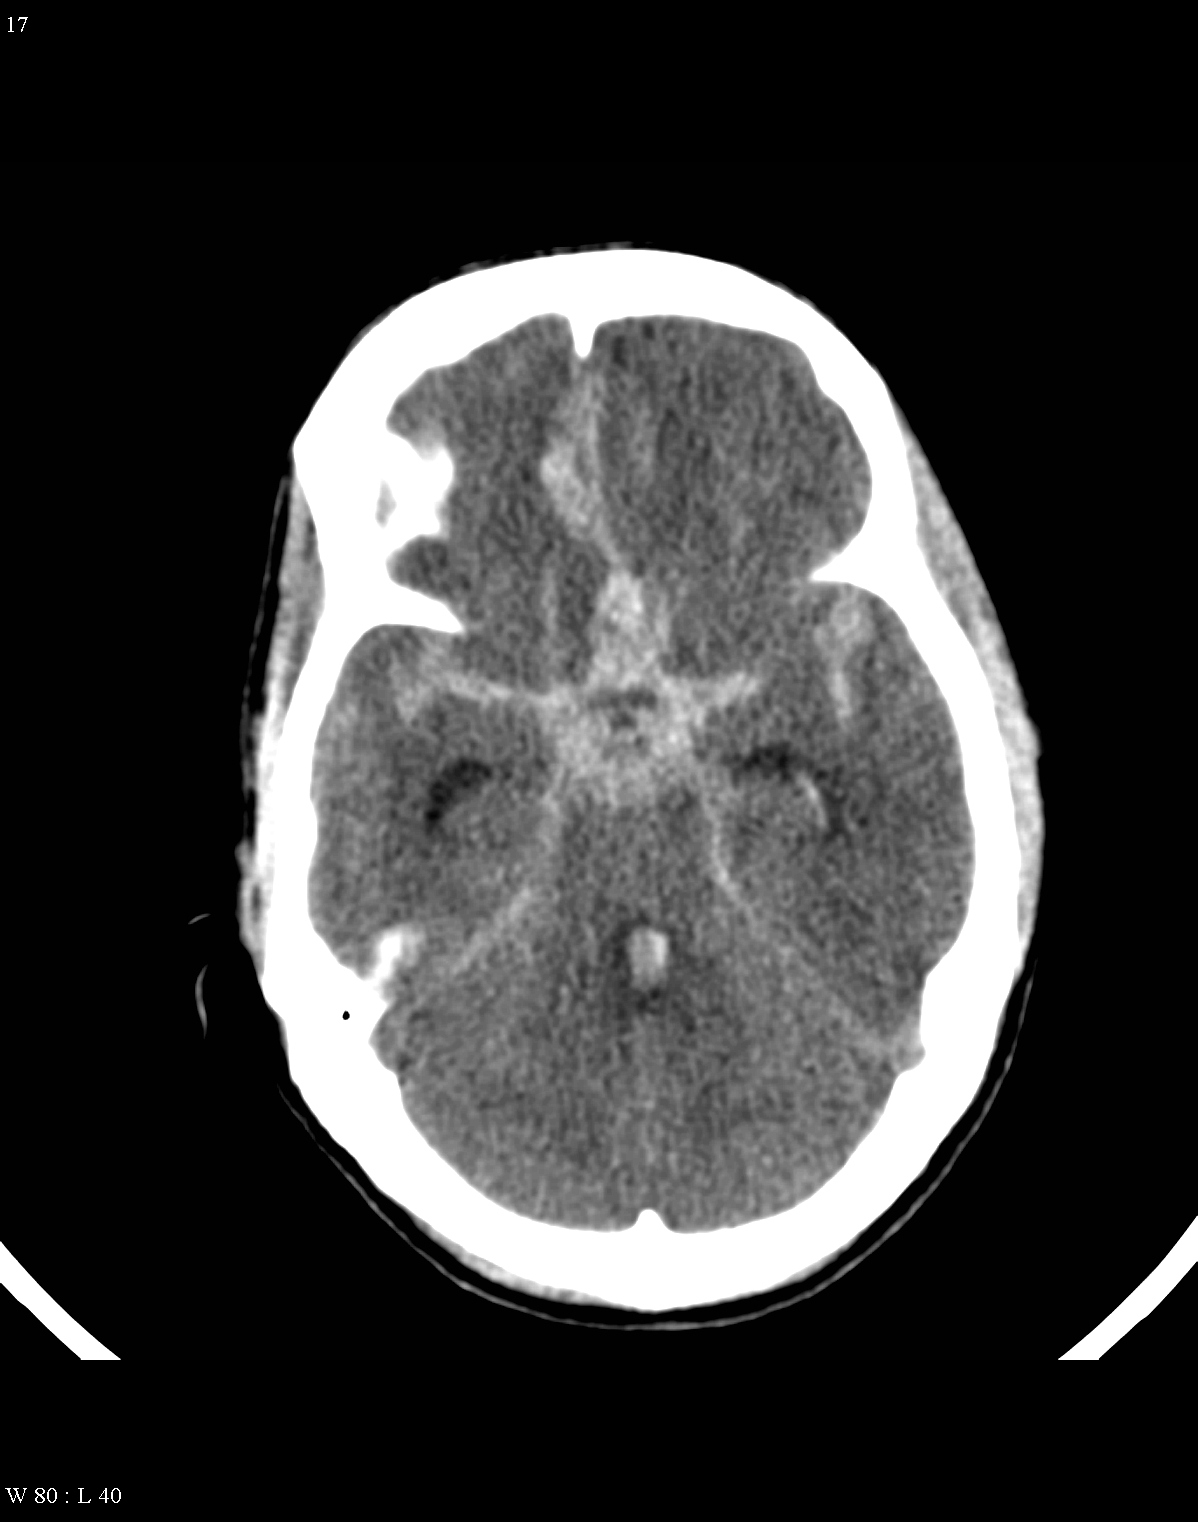

Fresh hemorrhage on CT appears hyperdense, therefore hemorrhagic stroke and subarachnoid bleeding can be promptly diagnosed with CT examinations.

The remaining (5%) of the patients can suffer spontaneous subarachnoid hemorrhage that most often results from brain aneurysm (on the branches of Circle of Willis) or from vascular malformations.

On CT images acute bleeding always presents as hyperdensity. (One has to keep it mind that hyperdensity of the blood is affected by the hematocrit levels, hence making the diagnosis more difficult.) Intraparenchymal blood is dominated by a destructive appearance (mass-effect) and it is surrounded by hypodensity as a sign of perifocal edema. It often breaks into the ventricles. In patients lying in a supine position they collect (sediment) at the occipital horn of the lateral ventricles, creating a hyperdense liquid-to-liquid levels. Later on, the density of blood decreases and shows a peripheral ring or rim-like contrast enhancement without mass-effect.

Although, subarachnoid hemorrhage (SAH) is most often caused by the rupture of a berry aneurysm, arteriovenous malformation (AVM) and trauma can also lead to it. SAH is typically located at the basal subarachnoid spaces, which then propagates along the lateral fissures or it fills up the interhemispheric fissure till the convexities. The main collection of the blood is usually indicative of the source of origin. In cases of parenchymal spread the mechanism, whether it broke in, or it broke out from the parenchyma could represent a differential diagnostic challenge. When accompanied by brain edema, the consequent herniation can result in parenchymal infarcts as well.